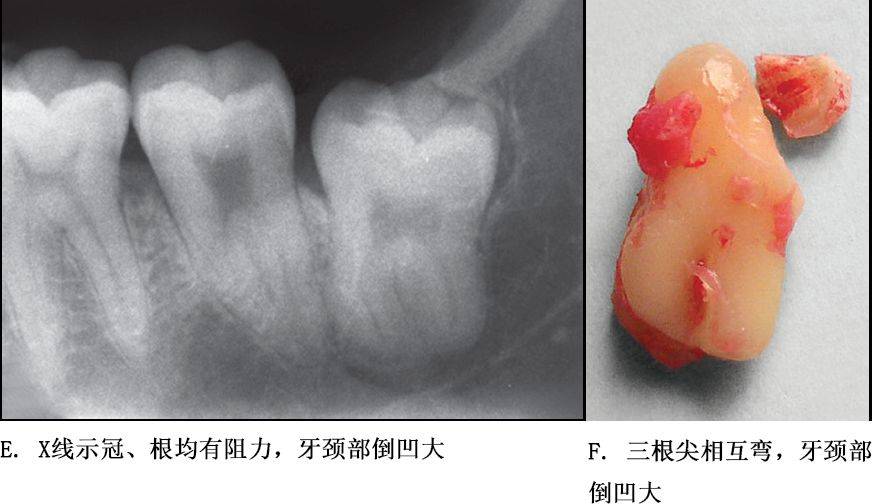

牙根阻力以多根牙、根分歧过大、特长根、U形根、牙颈部倒凹大者阻力较大根尖区以近中弯曲、多向弯曲、根尖肥大者牙根阻力较大。

根部阻力较大者的智齿形态